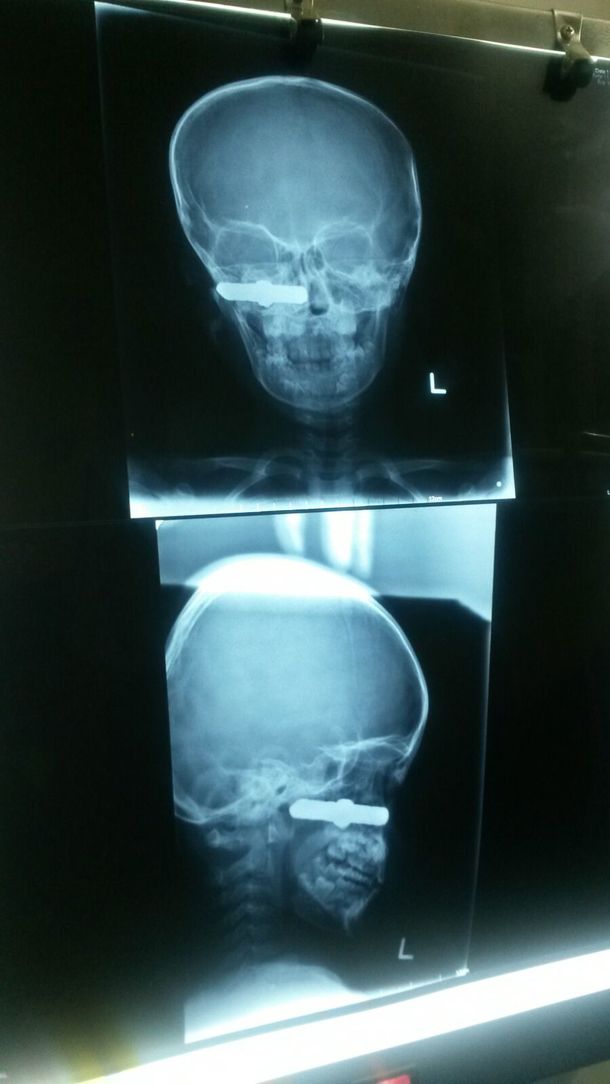

このレントゲン写真の通り、顔に銃弾が・・・。

すぐに手術室へ送られて摘出されたのが、7㎝もある鉄の棒。(正確には銃弾ではありませんでした。)

Bちゃんの術後の経過はとても良く、2週間後には退院。最後の数日は、院内を三輪車で走り回るほど元気になっていました。それにしてもBちゃんは幸運としか言えないです。もう少し奥へ打ち込まれてしまっていたら、脳や脊髄を傷つけていましたし、大きな血管もあります。また顔面の骨にも傷つくことなく、麻痺も無し。

お父さん曰く、狩猟のために天井の鴨居(というのか・・・?)に保管してあった銃(1m以上の長さ)をBちゃんのお兄ちゃんが取り出し、道に落ちていた鉄の棒(何かの部品と思われる)を銃へ入れ遊んでいた時に発砲してしまったのだそうです。

お父さんは田んぼで作業中でしたが発砲音を聞いて慌てて来てみると、Bちゃんの顔に打ち込まれていたとのことでした。